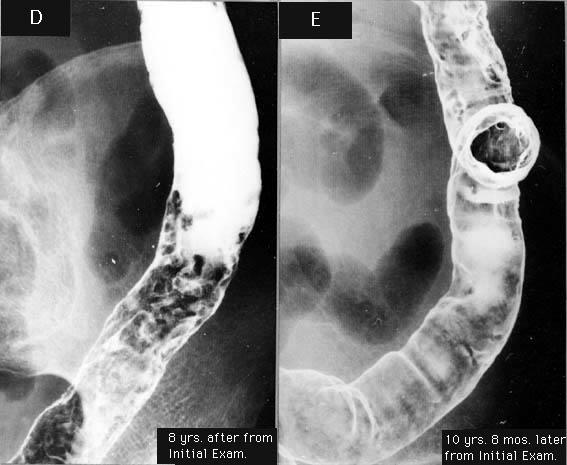

A case of ulcerative colitis showing a progression and remission of diffuse inflammatory polyposis during over a ten-year period.

Large intestine(Colon)/Descending colon

X-ray